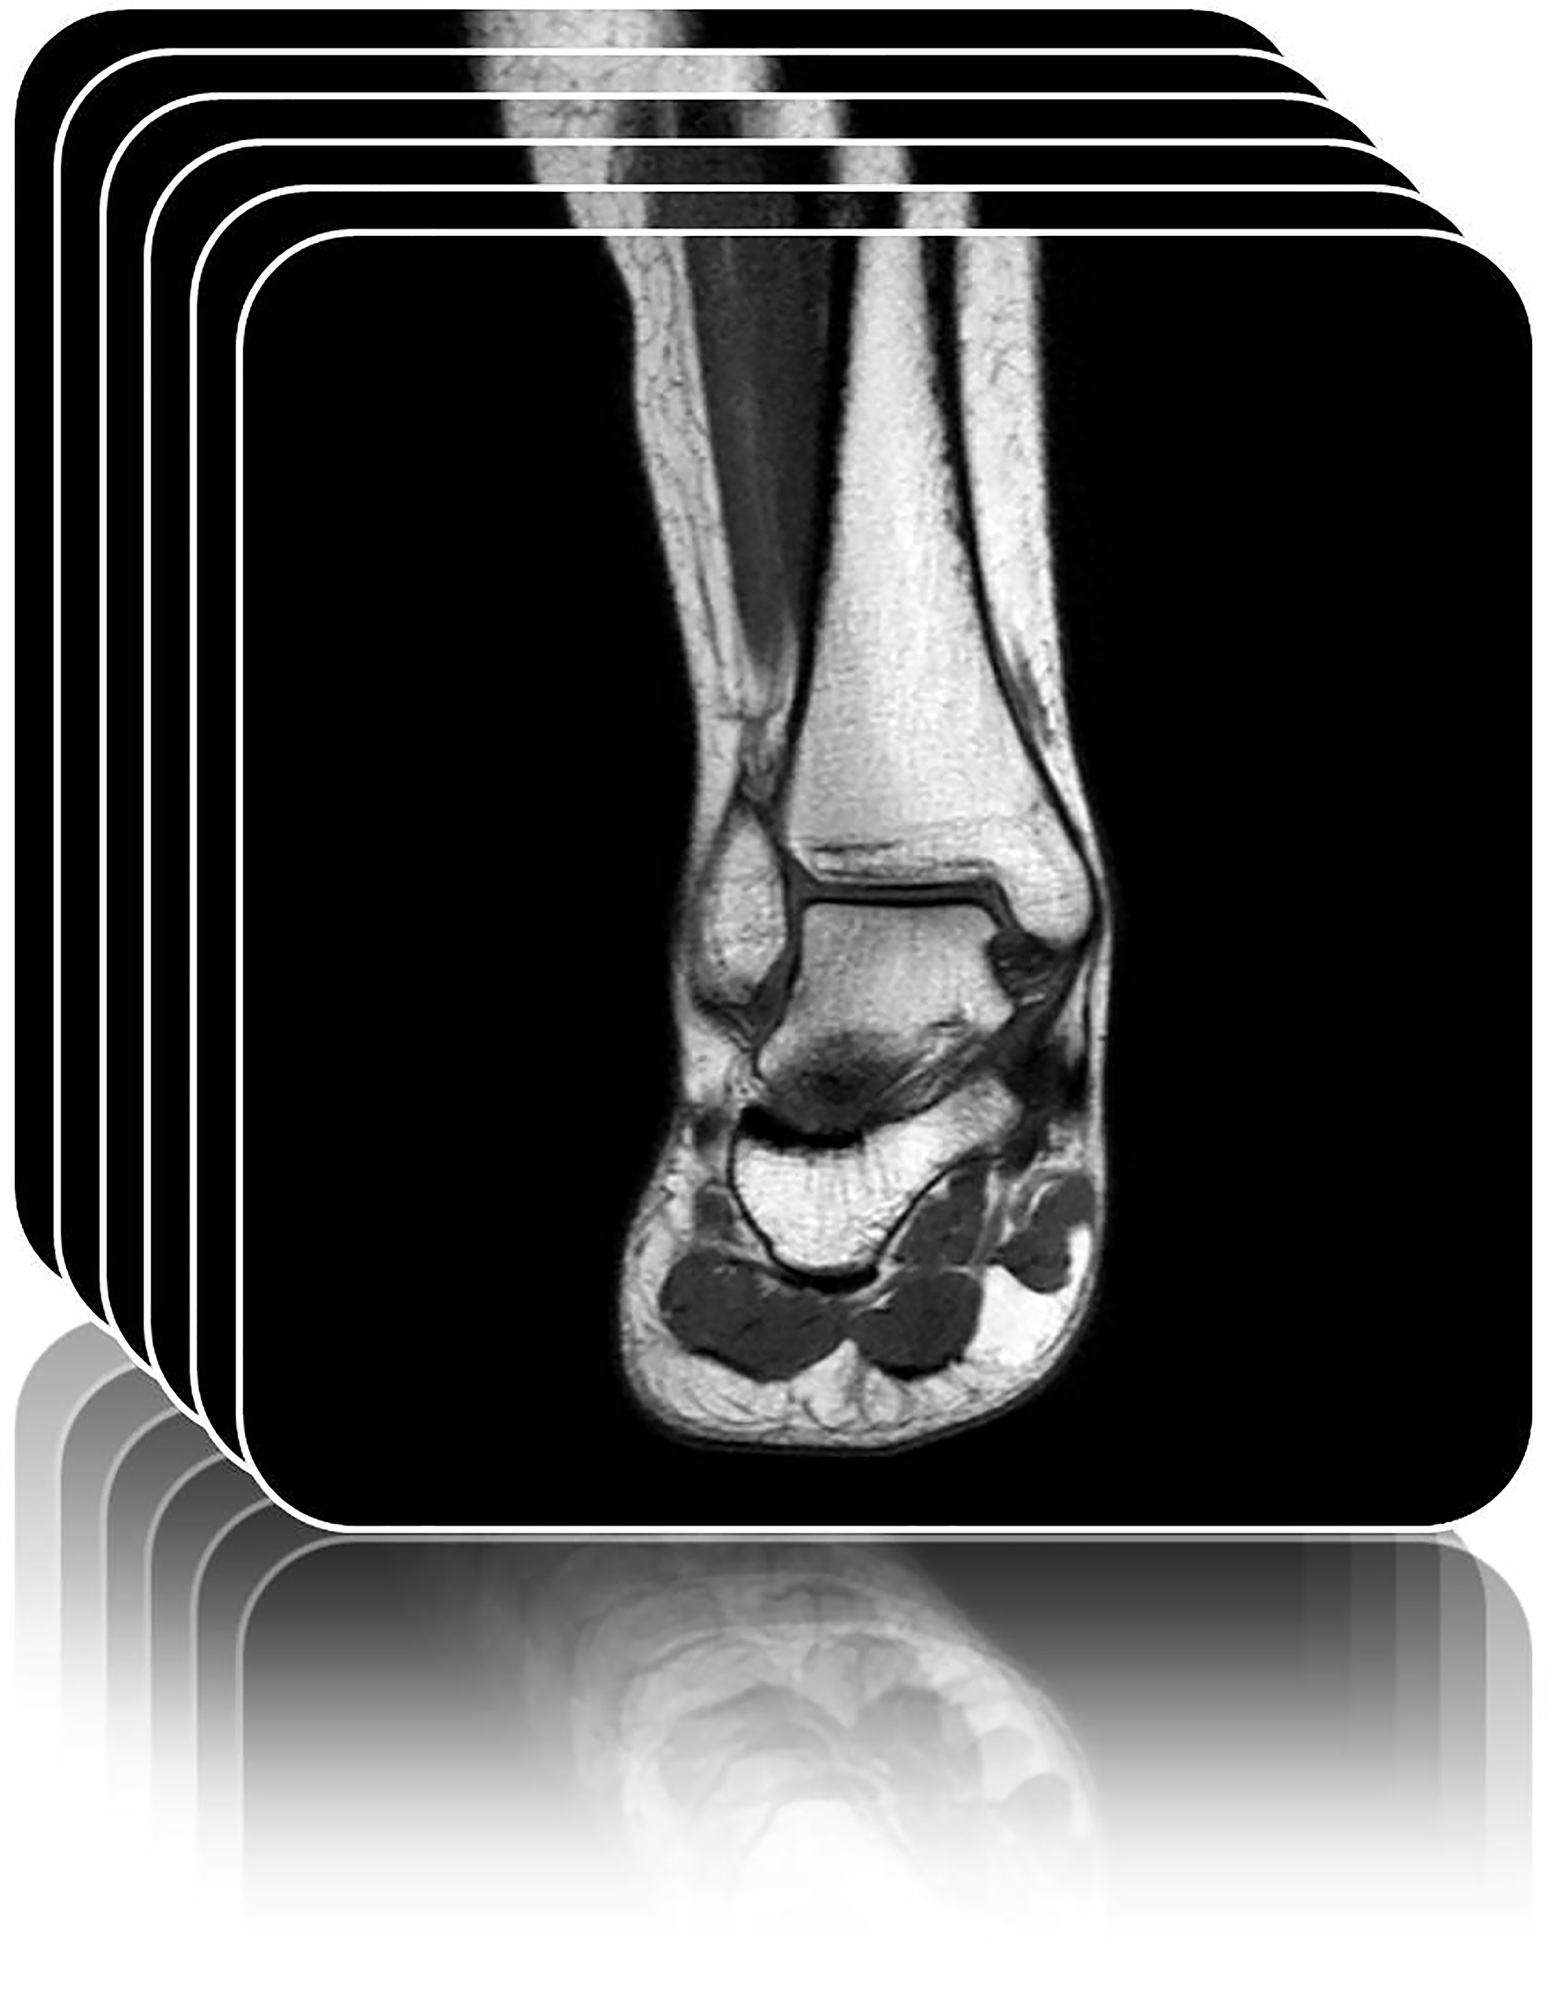

From routine checkups to treatments for surgery, Weil Foot & Ankle Institute is equipped to handle all your podiatric needs. To help you understand your options, we’ve included descriptions of some of our leading services on this page.